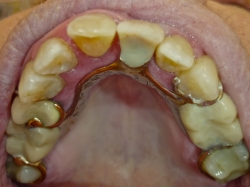

Unitorprotese

Denne form for delprotese er den mest almindelige, da den fylder minimalt i munden. Yderligere kan den udvides med flere tænder, hvis der på et senere tidspunkt skulle blive behov for det. Læs mere under udvidelse af protese. Den sidder fast i munden ved hjælp af bøjler, der er støbt efter formen på dine egne tænder, hvilket sikrer at den er yderst stabil. Protesen bliver fremstillet i krom og kobolt, hvilket gør at den er meget brudsikker.